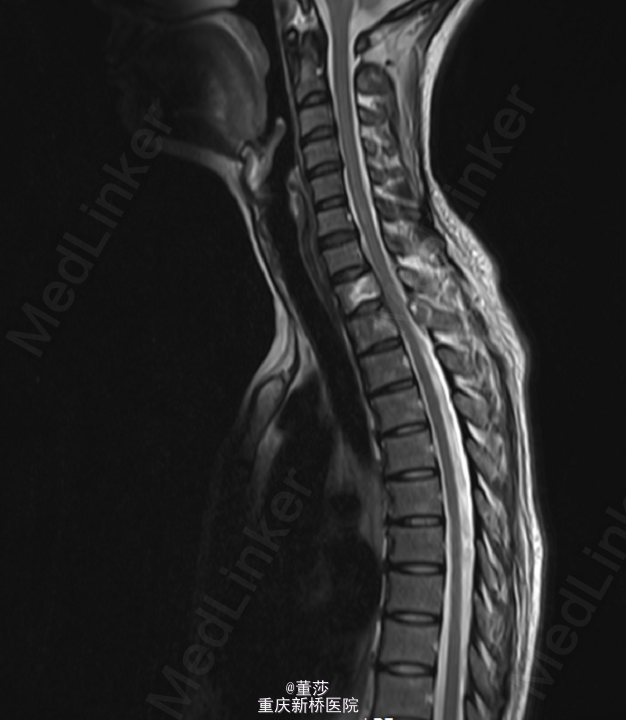

患者,女,38岁,因“右肩背部疼痛2月”入院。

患者2月前无明显诱因下出现右肩背部疼痛,不剧可忍,伴颈部放射痛,偶有右上肢麻木。

PET-CT:右肺肿块,考虑周围型肺癌,右肺门及纵膈多发淋巴结转移,T1及T2椎体及右侧附件骨转移;左颈部肿块针吸穿刺病理:转移性腺癌.

初步诊断:1.胸椎肿瘤:转移癌/肺恶性肿瘤。全身麻醉下行“胸椎恶性肿瘤后路肿瘤切除,椎管减压、内固定术”,术中予椎体内填充骨水泥,C5,C6,C7各打入一枚颈椎侧块螺钉,T3、T4两侧各打入一枚椎弓根螺钉,C臂机透视提示螺钉位置可。